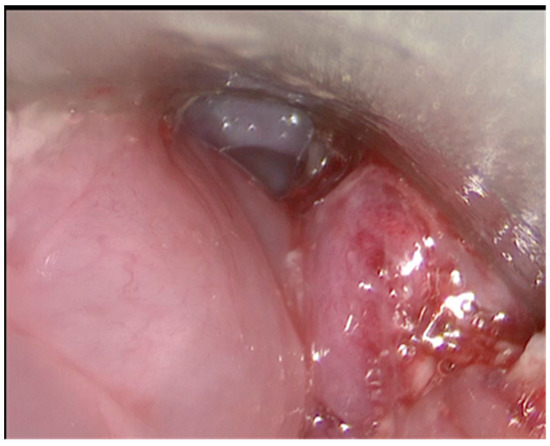

| Post operative revascularisation assesment | none | none | Endoscopic at day 0 and day 4 |